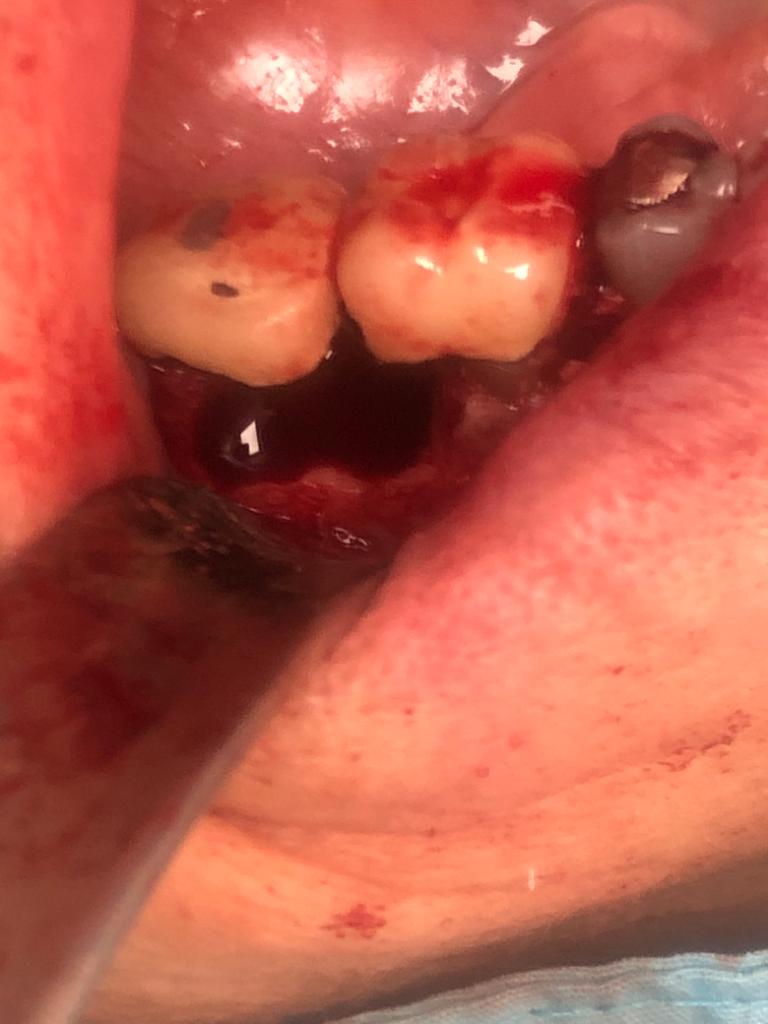

Lo cierto es que las raíces  ya estaban bastante separadas de el resto de los molares correspondientes por su destrucción, lo que nos permitió la extracción de estas raíces en concreto. Teniendo en cuenta también que las raíces mesial y distal de cada molar no estaban unidas entre sí, sino que había una separación entre ellas.

La técnica quirúrgica para este menester es parecida a una apicectomía, pero en lugar de quitar solo el ápice radicular quitamos toda la raíz dental. Así pues lo que se hizo fue extracción de la raíz distal del primer molar y extracción de la raíz mesial del segundo molar. Con lo que la prótesis sigue teniendo dos pilares.

Con la secuencia de imágenes se comprende muy bien la técnica quirúrgica realizada.